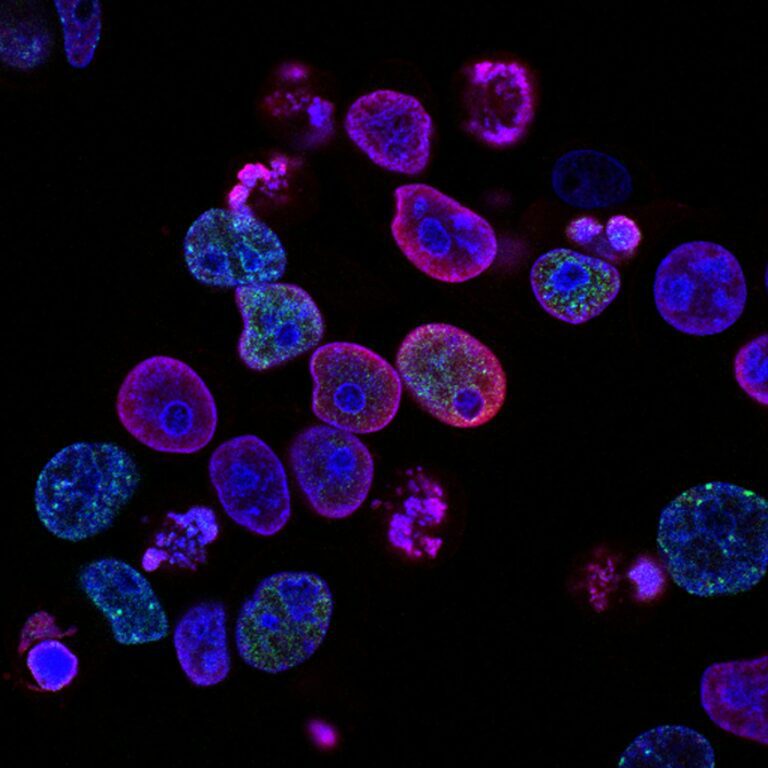

Μια πολύπλοκη σχέση ισορροπίας εν δράσει (Αναδημοσίευση με μετάφραση από: PROJECT CBD, “CANNABIS & THE IMMUNE SYSTEM: A COMPLEX BALANCING ACT” https://www.projectcbd.org/science/cannabis-and-immune-systemBY MARY BILES, ON MAY 08, 2019) Ένα νέο κύμα έρευνας δείχνει ότι τα κανναβινοειδή έχουν ένα προσαρμογόνο, ανοσοδιαμορφωτικό αποτέλεσμα, αντί απλώς να καταστέλλουν την δραστηριότητα του ανοσοποιητικού, όπως νόμιζαν κάποιοι. Η Cannabis sativa καταναλώνεται για λόγους υγείας και διατροφής εδώ και χιλιάδες χρόνια. Πολλοί αρχαίοι πολιτισμοί, από τους Κινέζους μέχρι τους Έλληνες, περιελάμβαναν την κάνναβη στην φαρμακοποιία τους. Τότε, κανείς δεν αμφισβητούσε το πώς ή το γιατί η κάνναβη απαλλάσσει από τον πόνο και ηρεμεί. Ήταν ένας χρήσιμος…